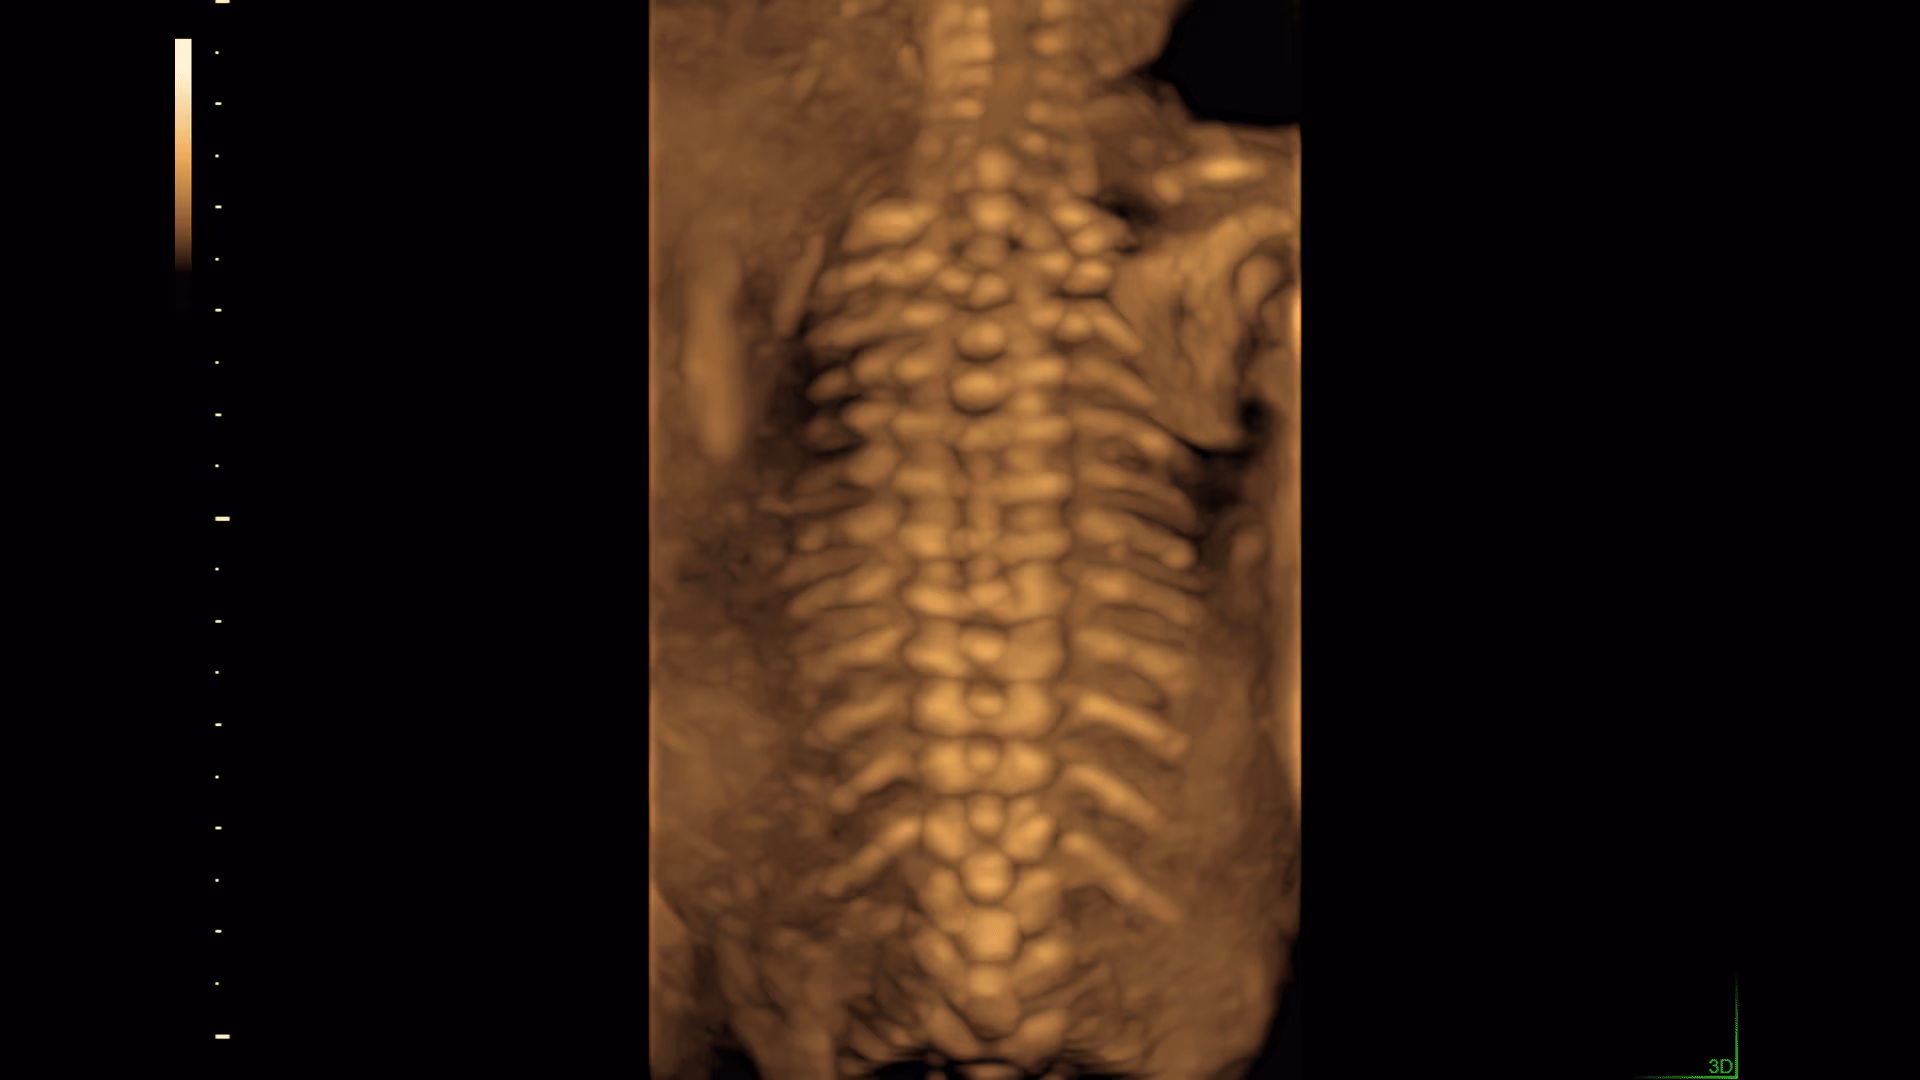

Sistema ecografico per ostetricia, ginecologia e fertilità

VOLUSON S8 con Touch panel

- 3D Uterine Trace

- Immagini veloci chiare e uniformi

- Dettaglio e risoluzione di contrasto eccezionale

- Visualizzazione dei piccoli vasi e dei bordi nel cuore fetale con RadiantFlowTM

- HDlive: tecnologia di rendering 3D/4D di Voluson che trasforma i dati ecografici in immagini più realistiche con profondità, illuminazione e texture migliorate